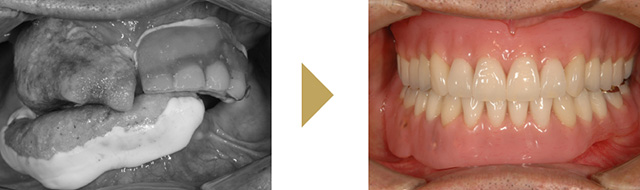

多くの歯を失った難症例にも対応します。

〜All-On-4,All-On-6〜

歯の先進国の欧米では広く普及している治療法です。

総入れ歯や多くの歯を失った方に4本から6本のインプラントをバランスよく骨に埋入して、連結した人工歯を支える治療法です。埋入手術当日に固定式の仮の歯をいれるので、その日のうちに噛む事が可能です。機能面はもちろん、審美的にも優れた治療法です。インプラント本数も少ないため、手術時間が短く、費用も抑えることが可能です。